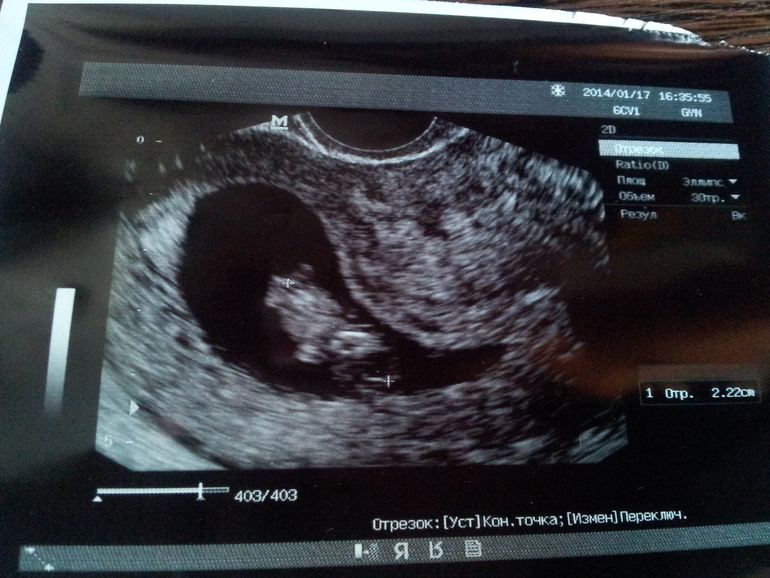

Оказалось, что все у нас хорошо! Предыдущий врач говорила, что не видит ручек и ножек. Ну не знаю, может он спинкой вверх лег... Когда вчера мне показали на мониторе мою крошку, то даже я там сразу же увидела крошечные ручки и ножки, скрещенные как у лягушки. )))) А между ножек мне показалось, что я разглядела писюн... )))) Но я думаю, что это мое воображение мне дорисовало картину. На таком сроке еще рано о таких вещах говорить, тем более врач мне ничего про пол не сказала. Но это все не так важно. Важно то, что ктр у моей малявочки уже 22 мм, растем! Сердечко бьется 174 уд/мин. Тонус правда сохраняется, но я его лечу. И моя крошечка соответствует 9-ти неделям! По всем таблицам. А если учесть, что 10 недель по месячным было только вчера, то отставание у нас незначительное. Всего лишь на неделю. Что с моим длинным циклом и неудивительно.

Ну и фоточка!

На фото не так хорошо видно, как на мониторе я разглядывала. Там прям четко было видно ручки, ножки, головку.